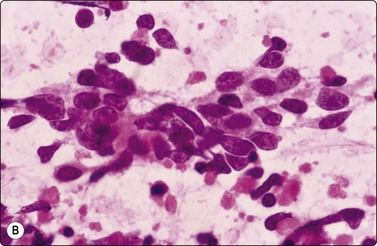

Small cell carcinoma (Figs 8.25-8.29)32,35,36,79,82,83

image

Fig. 8.25 Small cell carcinoma

Loose clusters with some dispersal and smearing artifact (Pap, HP).

Fig. 8.26 Small cell carcinoma

Pleomorphic poorly cohesive cells with little or no cytoplasm; nuclear molding (MGG, HP).

Fig. 8.27 Small cell carcinoma

Small loose cluster showing absence of cytoplasm, finely granular chromatin, inconspicuous nucleoli, nuclear molding and teardrop cells (H&E, HP).

image image image

Fig. 8.28 High-grade neuroendocrine carcinoma; small cell carcinoma

(A, B) Smears showing ‘intermediate’ morphology. Loose aggregates of fragile cells with traumatization artifact and nuclear molding but some background cytoplasm (A, Pap, MP; B, H&E, HP). (C) Tissue section of resected peripheral stage 1 small cell carcinoma (H&E, HP).

image image image image image

Fig. 8.29 High-grade neuroendocrine carcinoma

Variable morphology including small cell and large cell patterns. (A) Low-power smear appearances of small cell carcinoma; (B) Higher-power examination shows some large cells with prominent nucleoli (A, H&E, LP; B, H&E, MP). (C,D) Tissue sections of resected peripheral stage 1 tumor showing areas of geographic necrosis and a predominance of large cells with prominent nucleoli (C, tissue section, H&E, LP, Inset, HP; D, tissue section, H&E, HP). (E) Positive immunostaining for chromogranin in resected specimen (E, tissue section, IPOX, HP).

Criteria for diagnosis

Small or medium-sized cells with little or no cytoplasm (larger than in sputum),

Dispersed cell presentation; some clusters, including some small tight groups,

Nuclear molding and engulfment; irregular nuclei,

Uniform finely or coarsely granular nuclear chromatin; small nucleoli,

Tear-drop cells, smeared cells and streaks of nuclear material,

Engulfment of apoptotic bodies,

Numerous mitotic figures.

This group of lung carcinomas is the most aggressive of the common types, having a mean survival of less than 6 months without treatment. Small cell carcinoma is virtually unheard of in non-smokers, while for carcinoid and atypical carcinoid the smoking association is much weaker. It is important to categorize this neoplasm accurately because, in general, chemotherapy rather than surgery will be used in management. In addition, chemotherapy regimens are different from those used for inoperable non-small cell carcinomas. This group is fairly homogeneous in terms of its biology but is more heterogeneous morphologically. Attempts at morphological subclassification have been made; however, the larger ‘intermediate’ and smaller ‘oat cell’ subtypes are not reliably separable by expert pathologists and do not have significantly different behavior or response to therapy. The latest WHO classification therefore does not subcategorize small cell carcinoma although it does recognize mixtures with other types of carcinoma.217

Cytology is very successful in diagnosing small cell carcinoma in sputum and pleural fluid; in fact, sputum cytology may be more accurate than FNAC in typing this lesion. The criteria for the diagnosis of small cell carcinoma in aspirated material are similar to those in other sample types, but there are some important differences.

Page 226

Cell pleomorphism is so distinctive that a diagnosis of malignancy is seldom in doubt (Figs 8.25-8.27). The most immediate impression is the absence or sparseness of cytoplasm rather than the small size of the neoplastic cell (Figs. 8.26 and 8.27). In fact, the cell nuclei may appear larger than similar cells in sputum and this may mislead one into making a diagnosis of non-small cell carcinoma. This difference in size between sputum and aspirated material is due to degenerative changes and shrinkage in sputum. It is sparseness of cytoplasm rather than size which is the most helpful initial clue in differentiating the lesion from other pulmonary carcinomas.

The combination of dispersal with clustering is also important, especially when other small cell neoplasms enter the differential diagnosis (Fig. 8.25). Lymphomas generally do not display such cell cohesion, although large fragments may be dislodged, and in some cases lymphoid cells may form clusters or packets.

Fragility of nuclei is emphasized by tear-drop cells or streaks of smeared nuclear material,226 and the close nuclear apposition and molding so commonly seen in sputum are also evident (Figs 8.26 and 8.27). Uniform coarsely granular ‘salt and pepper’ nuclear chromatin is also a well-recognized feature of this cancer in other sites, but one point of difference from sputum is the frequency of small nucleoli in aspirated material; they are less commonly seen in sputum. This may also be related to the better preservation of cells removed directly from tumor; small nucleoli are also often seen in bronchial brush material. Mitotic figures are usually easily found.